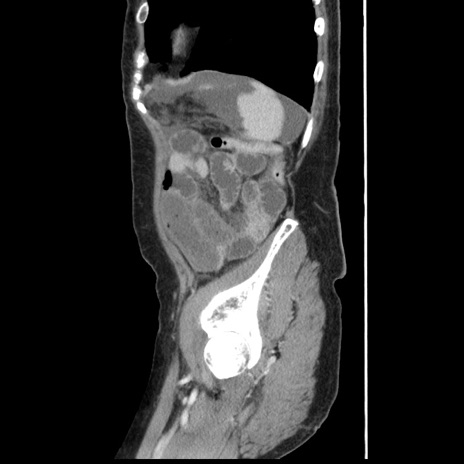

症例1(矢状断像)

【症例】80歳代女性

【主訴】腹痛

【現病歴】8時間前から腹痛あり来院。

【既往歴】糖尿病、脂質異常症、子宮体癌にて子宮全摘術

【身体所見】意識清明・会話良好だが腹痛で苦悶様、全腹部にわたって反跳痛と圧痛あり

【データ】WBC 13600、CRP 0.14、LDH 224、CK 90